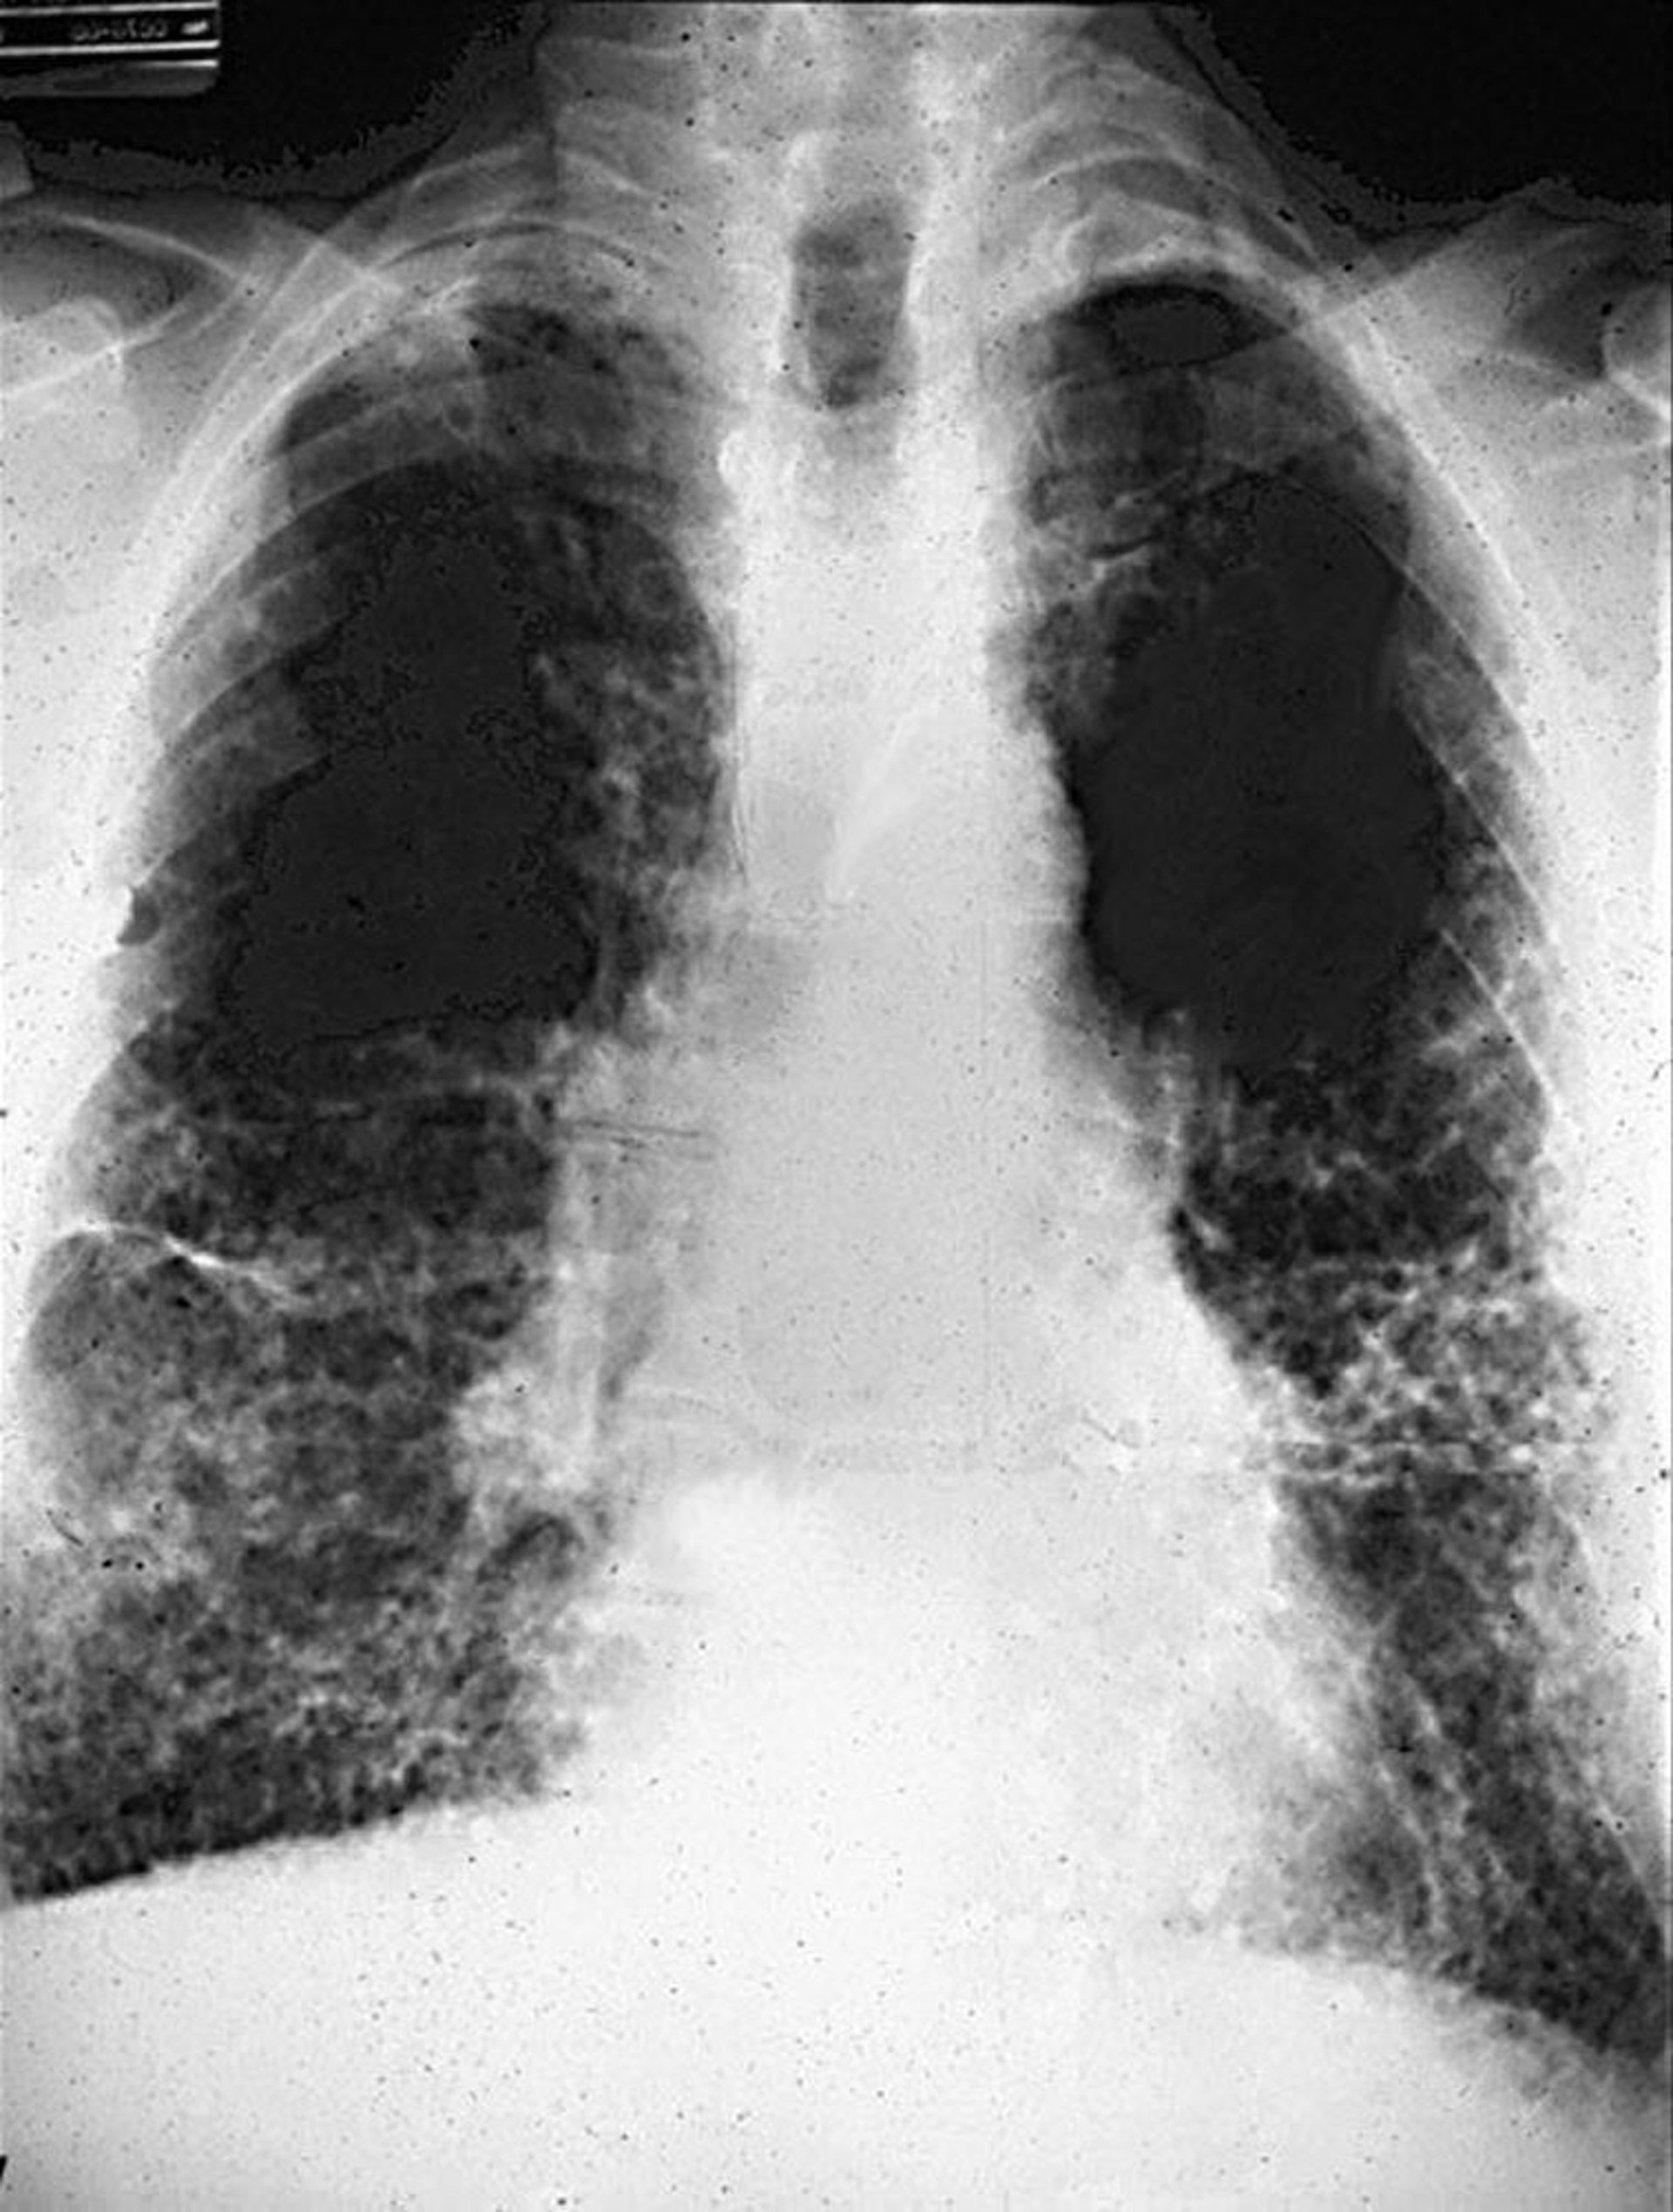

A radiografia do tórax revela opacidades bilaterais reticulares ou nodulares, significando fibrose, geralmente na periferia dos lobos inferiores, com ou sem alterações pleurais. A TC de tórax oferece maior sensibilidade na identificação de anormalidades pleurais e parenquimatosas e tipicamente mostra o padrão habitual de pneumonia intersticial da fibrose pulmonar. A presença de faveolamento, que pode envolver os campos pulmonares médio e inferior, indica uma doença mais avançada.

O sistema da Organização Internacional do Trabalho (International Classification of Radiographs of Pneumoconioses) é utilizado para caracterizar a presença e gravidade de pneumoconioses com base no tamanho, forma, localização e profusão de opacidades. A asbestose provoca opacidades reticulares, predominantemente no lobo inferior. As linfadenopatias hilar e mediastinal não são características e sugerem diagnóstico diferencial.

Alterações reticulares com faveolamento na asbestose.

Imagem cedida por cortesia de David W. Cugell, MD.